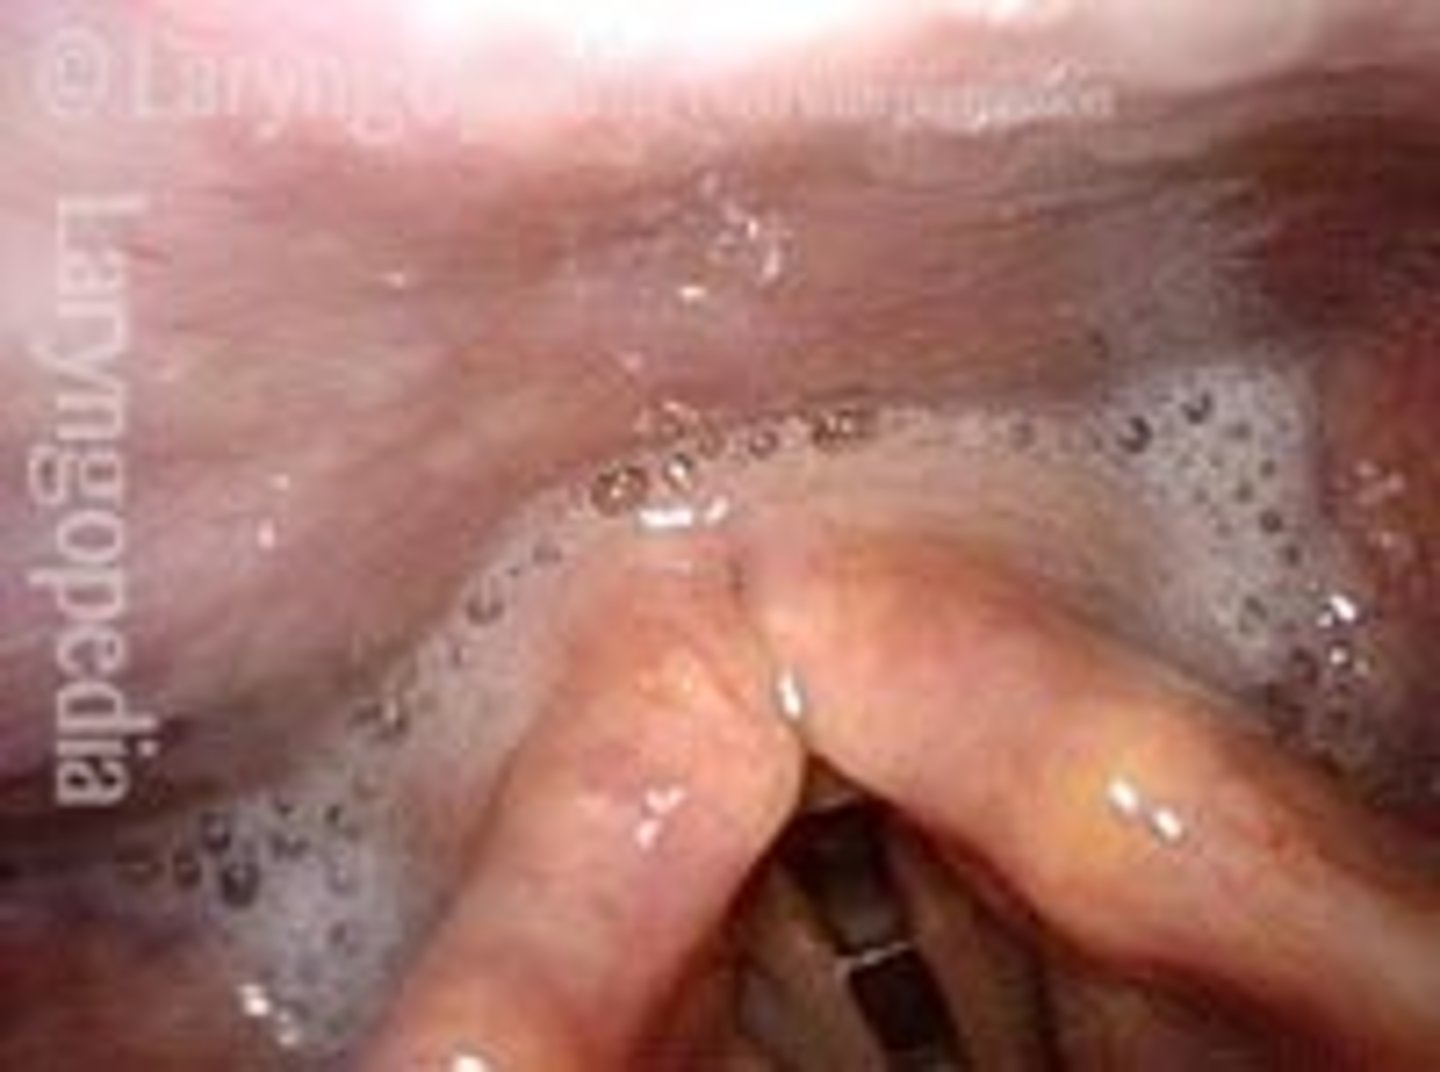

What do you see in the following picture?

Secretions pooling in the pyriform sinus